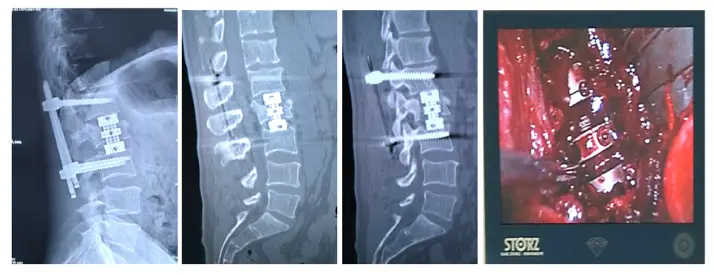

Видеоэндоскопический спондилодез телескопическим эндопротезом и чрескожная мини-инвазивная транспедикулярная стабилизация и при оскольчатом переломе второго поясничного позвонка.